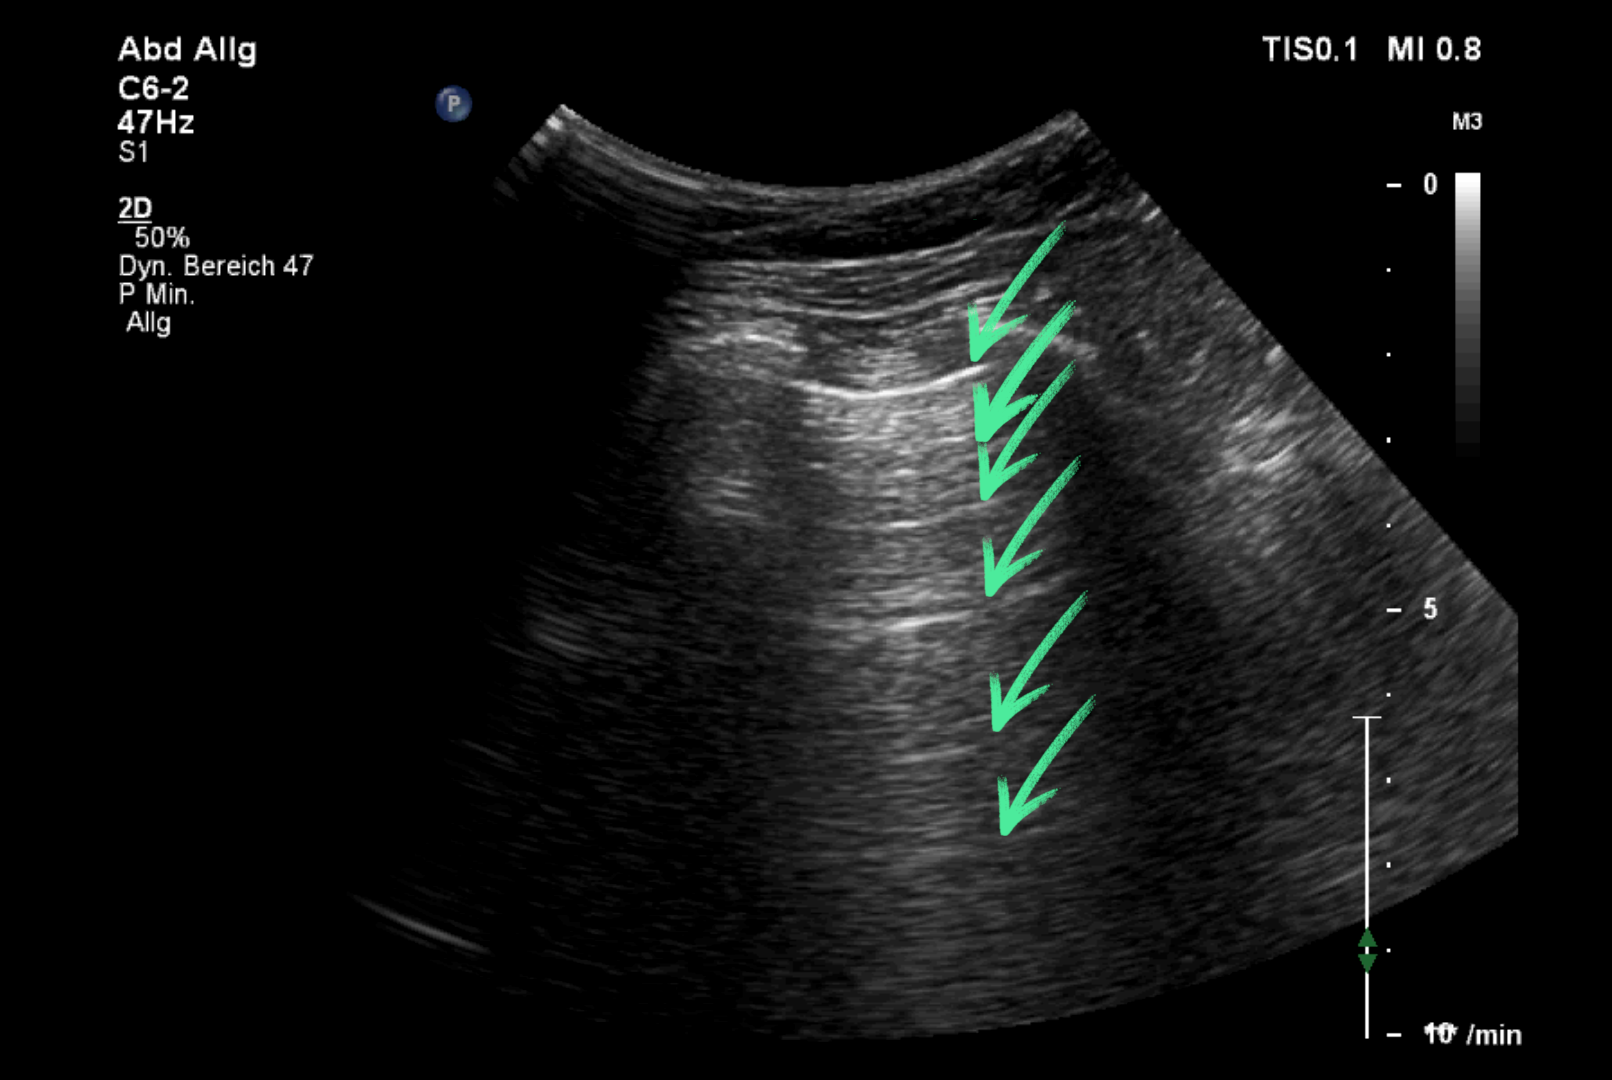

Lungensonographie::

Die parallel zur Pleura parietalis verlaufenden, in regelmäßigen Abständen zur Pleuralinie auftretenden, echoreichen Linien sind verursacht durch Reverberationen der Pleura parietalis.